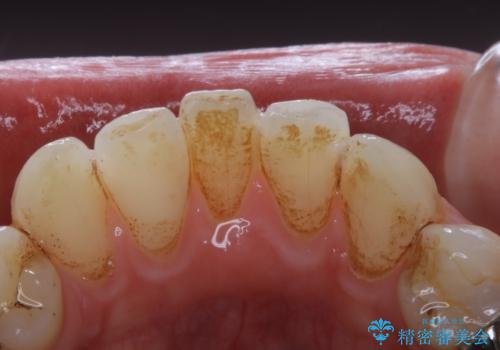

- 歯科がかなり久しぶりで、今後虫歯治療予定のためまずはクリーニングを希望されました。PMTC60分コースを行いました。

歯の表面に、茶色く色が残っている所がありますが、これは詰め物の変色の所と、虫歯になっている所です。以前に、CR(コンポジットレジン)による虫歯治療がされています。

CRは経年的劣化や、着色してしまうことがあります。PMTCでクリーニングを行うと、古いCRが目立つことがあるため、気になる際は詰め替えを行います。

茶色くなっている部分が、着色なのか、劣化なのか、虫歯によるものなのかは判別が難しいことがあります。そのため、定期的にPMTCを行うことで状態の確認が的確に行えます。